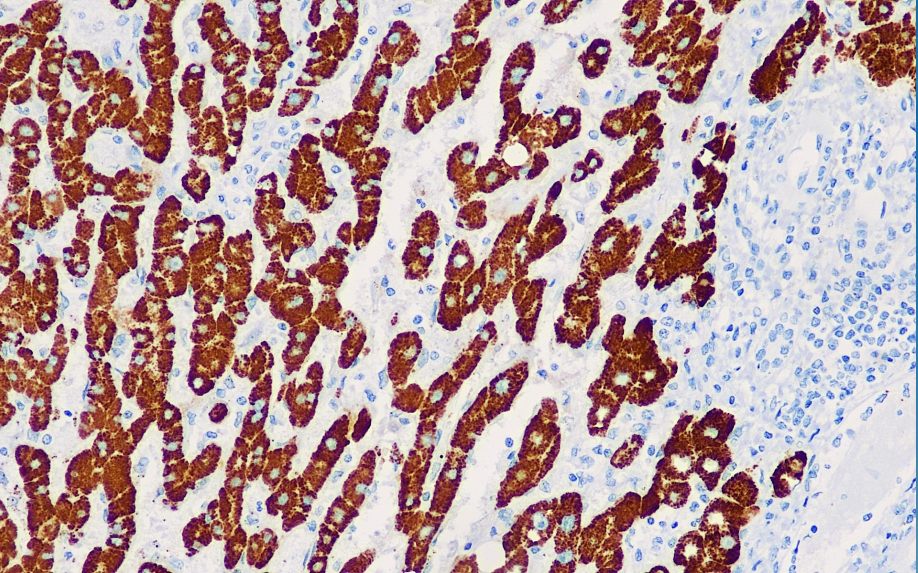

Cellular localization: cytoplasmic

Positive control: Liver

The antigen recognized by this antibody is present in normal human liver cells and most hepatocellular carcinomas, but does not react with many other human tumors, including gastrointestinal tumor cells. This antibody can stain the vast majority of hepatocellular carcinomas and is mainly used in liver tumor research.

Hepatocyte antibody reagents can specifically bind to hepatocyte molecular antigens. Immunohistochemistry kits containing hepatocyte antibody reagents are suitable for the precise diagnosis of hepatocellular carcinoma.